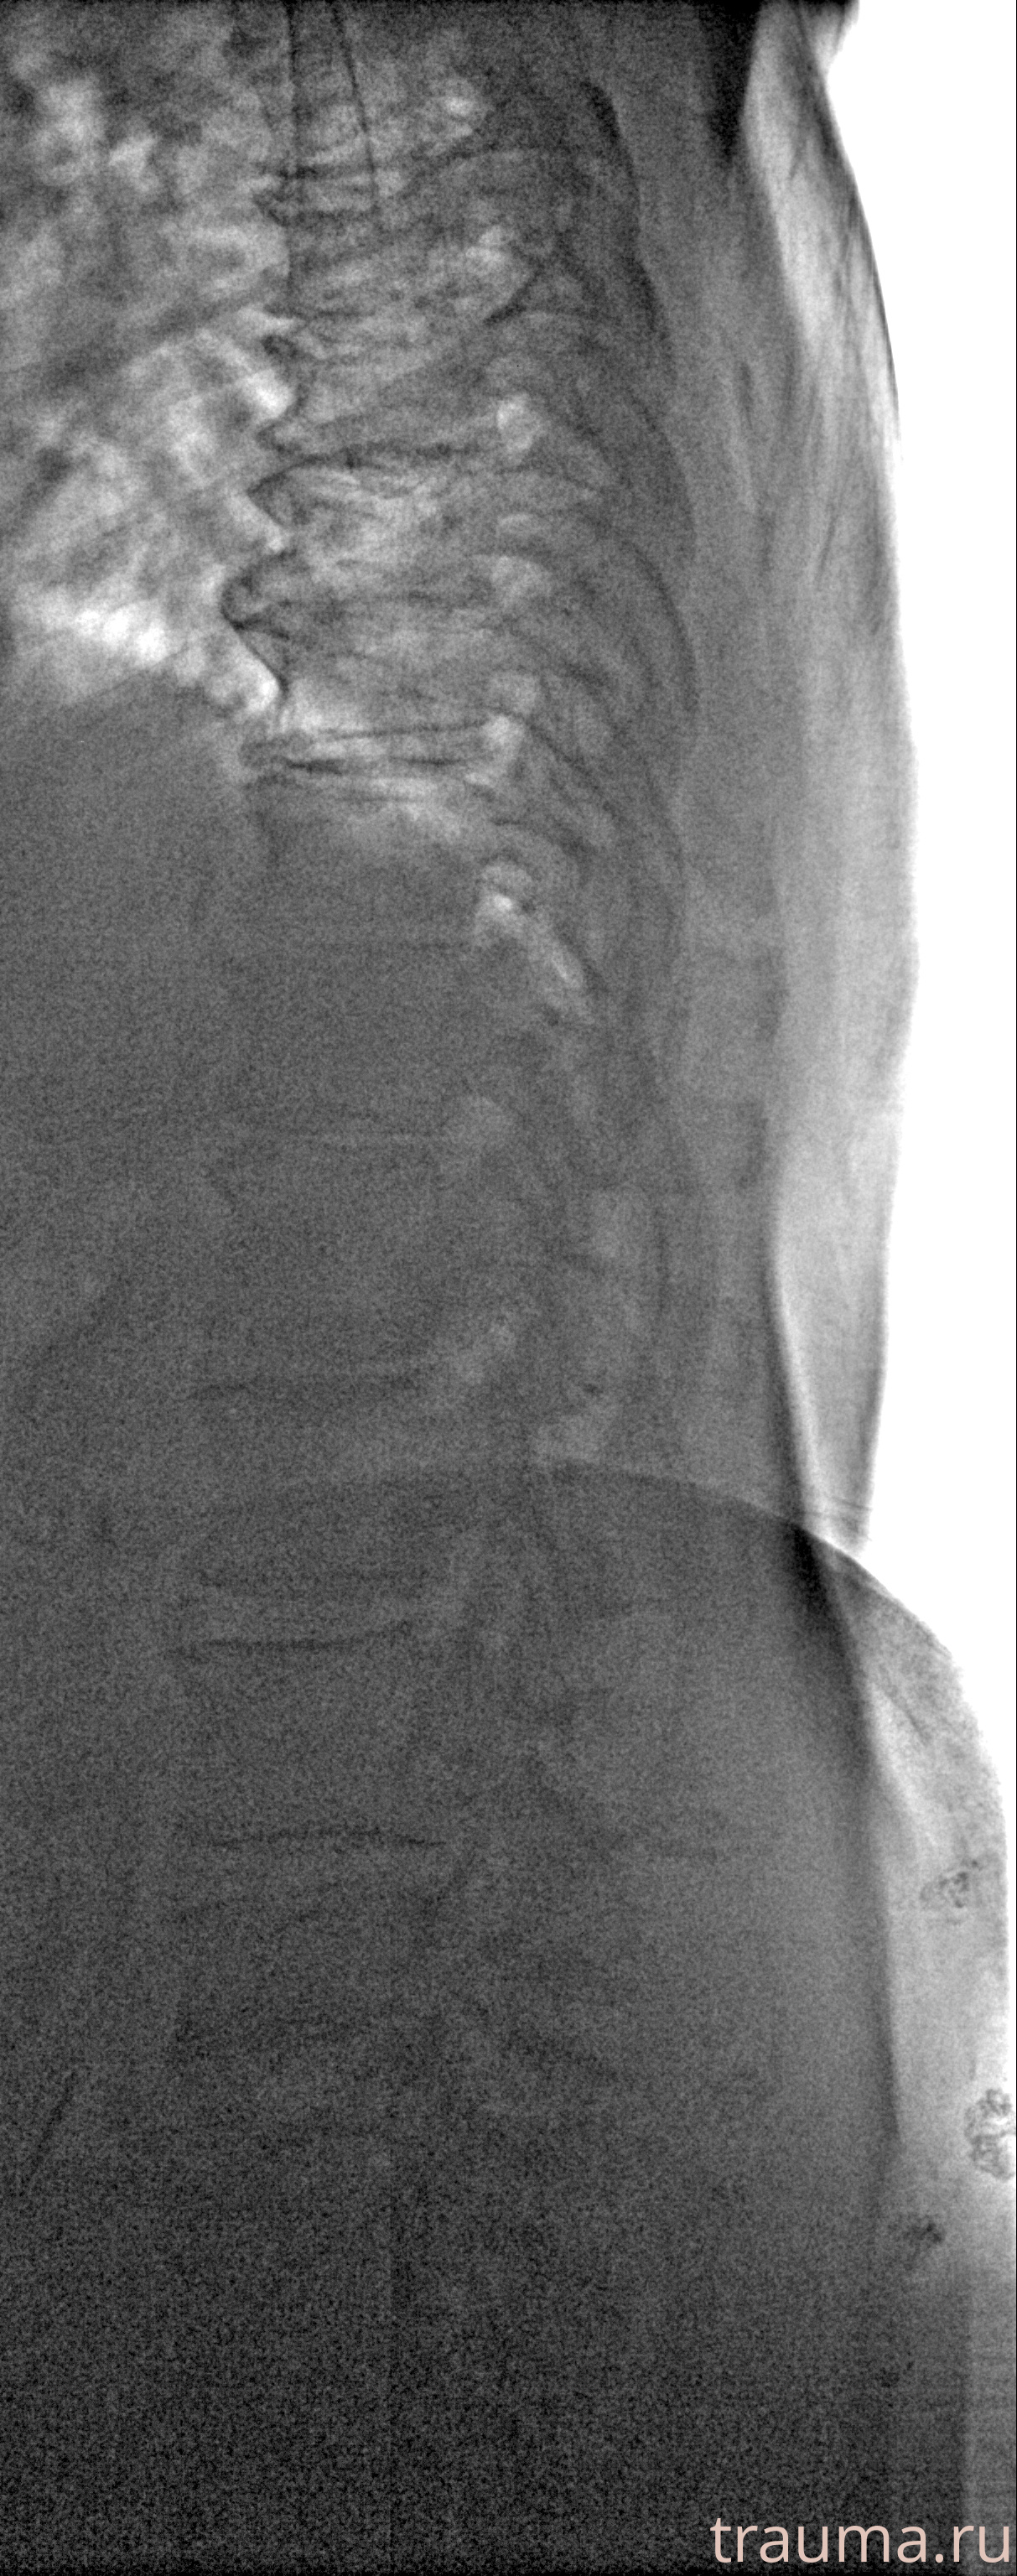

Рентгенограммы

Рентген на дому: по вашему адресу приезжает врач-рентгенолог, травматолог-ортопед с мобильным рентгеновским аппаратом, проводит диагностику травмы или заболевания, делает необходимые рентгенограммы, дает рекомендации по дальнейшему лечению. Получить качественные снимки в домашних условиях возможно благодаря уникальной методике, разработанной МосРентген Центром для института  Склифосовского